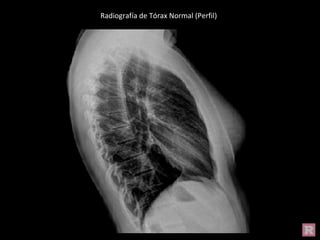

Radiografía de Tórax Normal (Perfil)